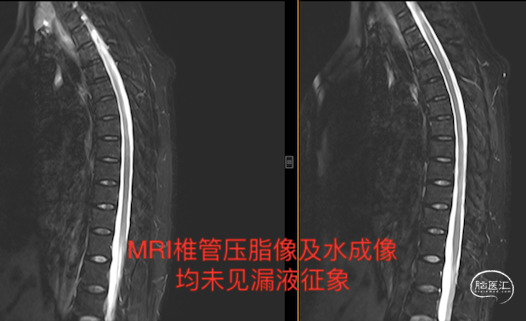

入院后头部MRI平扫及增强均未见异常,脊柱MRIT2压脂扫描如下图:

随后的水成像检查也未见异常。